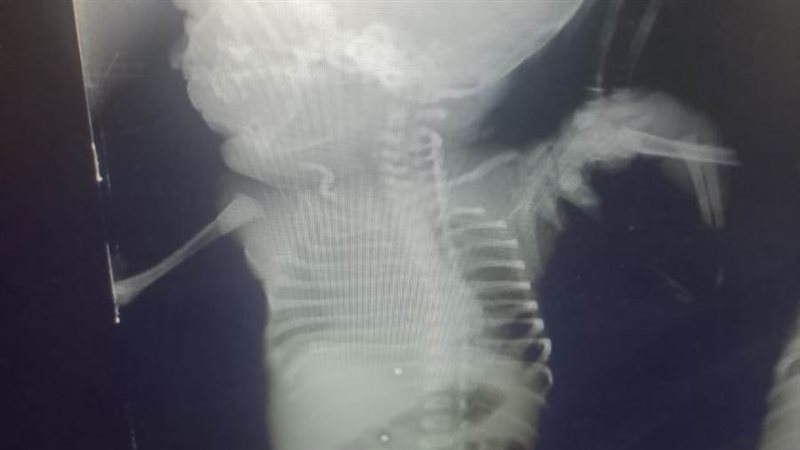

وأوضح الدكتور هاني جميعة وكيل وزارة الصحة بأنه تم استقبال الأم الحامل بقسم الطوارئ بمستشفى أبو حماد المركزي، بتشخيص مبدئي نزيف داخلي بالبطن، وهي في بداية الشهر التاسع من الحمل، مع اشتباه إصابة الرحم والجنين، وذلك نتيجة ادعاء تعدي من آخرين بطلق ناري "خرطوش" بالبطن مع وجود آثار لإصابات ظاهرية بالخرطوش، مع هبوط حاد بالدورة الدموية وانخفاض بضغط الدم، وبعد إجراء الفحوصات الطبية المختلفة، من موجات صوتية علي البطن والحوض والتحاليل اللازمة، تم التأكد من وجود نزيف داخلي بالبطن، وبعد مناظرة الحالة من أطباء النساء والتوليد وأطباء الجراحة العامة، تم حجزها بالقسم الداخلي ومنه إلى غرفة العمليات، للتدخل الجراحي العاجل، بعد الفحص الإكلينيكي للمريضة، حيث تم عمل استكشاف بالبطن، والذي أظهر وجود نزيف داخلي نتيجة اختراق الخرطوش لأمعاء المريضة، ليتم رتق الأمعاء، ووقف النزيف عن طريق أطباء الجراحة، هذا بالإضافة إلى إجراء عملية ولادة قيصرية، أظهرت اختراق الخرطوش لرحم الأم ووصوله إلي جسم الطفل، واستقرار عدد من طلقات الخرطوش بجسم الطفل من ناحية الظهر.